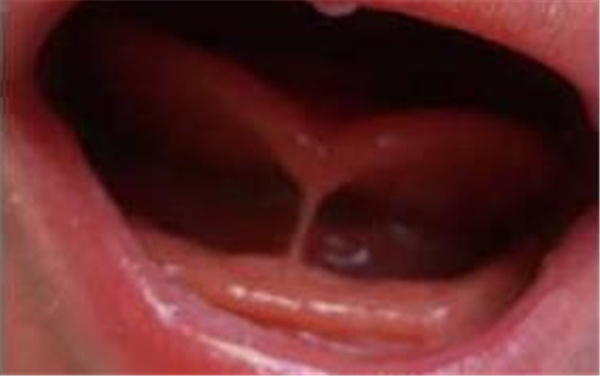

舌系带过短,又称舌固连,是较常见、轻微的先天畸形之一。表现为舌不能正常自由前伸,舌系带附着于舌尖稍后,勉强前伸时舌尖部变成“W”形,正中有切迹。因为舌尖上抬困难,出现卷舌音和舌腭音发音障碍,特别是【r】音,就是小时候大家说的大舌头,严重者舌前伸不能越过下唇。